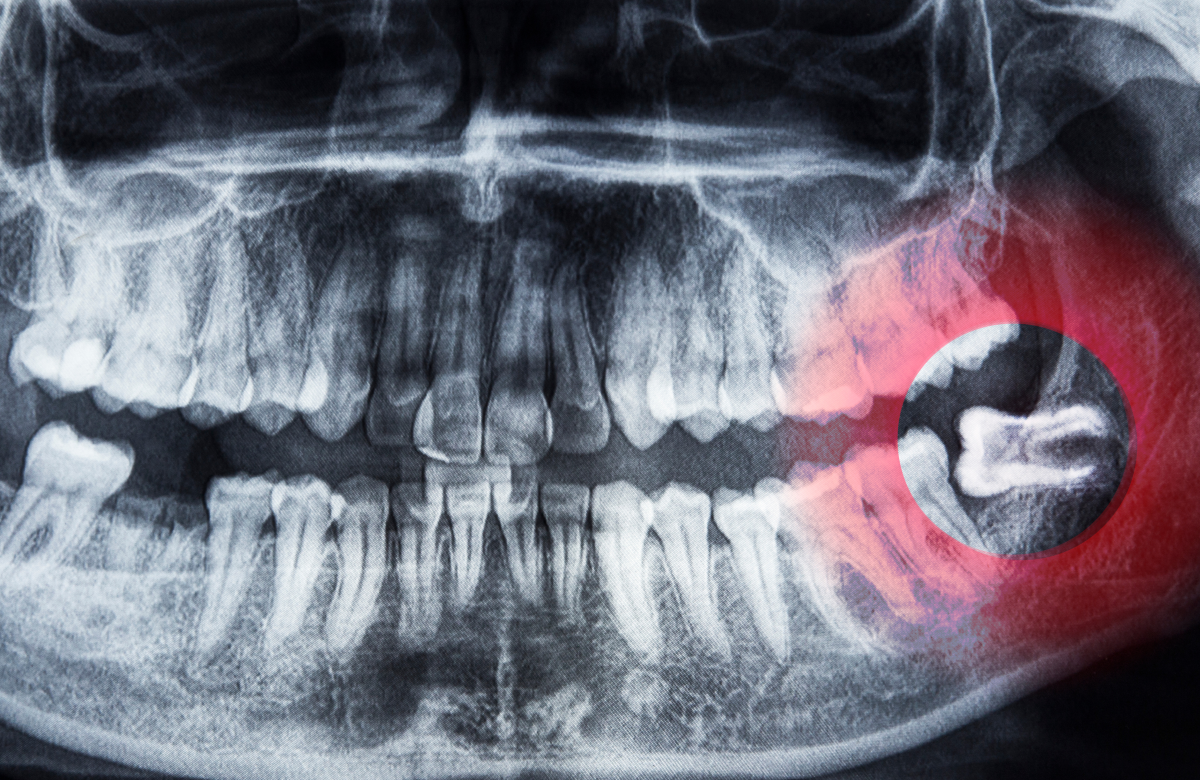

ฟันคุด คือ ฟันกรามซี่ที่สามซึ่งเป็นฟันซี่สุดท้ายที่จะขึ้นในช่องปาก โดยมักจะขึ้นในช่วงอายุ 17-25 ปี แต่ปัญหาที่พบบ่อยคือขากรรไกรมีพื้นที่ไม่เพียงพอ ทำให้การขึ้นของฟันคุดเกิดการผิดปกติในลักษณะต่างๆ ได้แก่:

- ฝังตัวอยู่ในกระดูกขากรรไกร (อาจอยู่ในแนวนอนหรือแนวเอียง โดยไม่โผล่พ้นเหงือก)

มีการใช้เครื่องเอกซเรย์ดิจิทัลและ CT Scan 3 มิติ เพื่อวางแผนการรักษาได้อย่างแม่นยำ พร้อมมาตรฐานการควบคุมการติดเชื้อในห้องผ่าตัดอย่างเข้มงวด